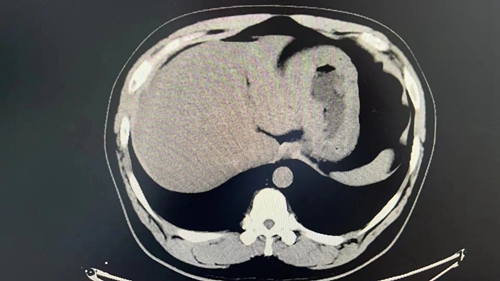

胃部腫瘤足足有10×10cm

檢查的結(jié)果比預(yù)想中的還要糟糕:腫瘤巨大,足足有10*10cm,占據(jù)了胃小彎側(cè),延伸至賁門(mén)下方;同時(shí)綜合普外科團(tuán)隊(duì)發(fā)現(xiàn)患者患有多發(fā)性膽囊結(jié)石,其中有小結(jié)石位于膽囊頸部,手術(shù)勢(shì)在必行。但李先生體重達(dá)200斤,且合并多種基礎(chǔ)病,此前還先后做過(guò)3次心臟支架手術(shù),心肺功能較差,手術(shù)風(fēng)險(xiǎn)極高。